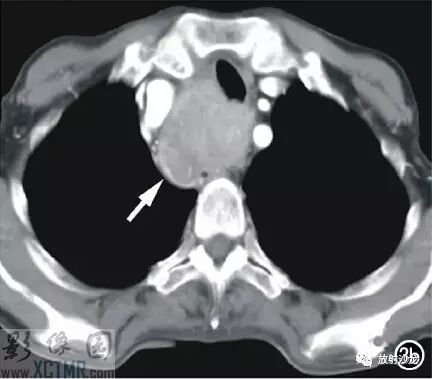

上消化道鋇餐:食管胸上段可見(jiàn)不規(guī)則充盈缺損,約5.6cm*4.2cm,黏膜結(jié)構(gòu)紊亂,管壁不規(guī)整,對(duì)比劑通過(guò)稍緩慢,會(huì)厭動(dòng)度不協(xié)調(diào),考慮食管癌(圖2)。CT:食管胸上段見(jiàn)軟組織腫塊,上自杓會(huì)厭披裂,下至主動(dòng)脈弓水平,腫塊邊緣清晰,密度均勻,增強(qiáng)掃描輕到中度不均勻強(qiáng)化,食管腔狹窄,氣管、右側(cè)甲狀腺、鄰近血管受壓移位(圖3),縱隔未見(jiàn)腫大淋巴結(jié),診斷:食管癌可能。